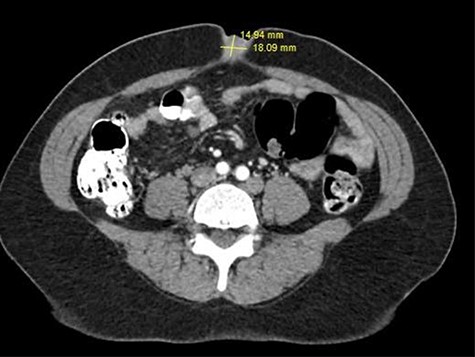

A 52-year-old female presented with complaints of increasing umbilical pain and swelling for a year. She described the pain as intermittent and daily. She denied any aggravating factors. There was no correlation with eating or movement, and she had no relief with Tylenol. Fourteen years ago, she had an umbilical hernia repair at an outside institution, per their documentation; this was done primarily, without mesh. She also had a colonoscopy and upper endoscopy a year prior, which was negative. Her past medical history was remarkable for uterine fibroids. On exam the abdomen was soft and non-distended; the umbilicus was tender to palpation, with no hernia defect palpable. There was no erythema or induration (Fig. 1). At this time the differential included a suture granuloma, benign or malignant mass. A computed tomography (CT) scan of the abdomen and pelvis relieved no hernia but there was an umbilical mass present, a thickened appendiceal tip, abutting a large uterine fibroid (Fig. 2). Tumor markers including carcinoembryonic antigen, carbohydrate antigen (CA) 19-9 and CA 125 were obtained and within normal limits. At this time it was decided that surgical intervention was warranted for increased concerns of malignancy, and a Sister Mary Joseph nodule could not be excluded. The patient was brought to the operating room for a diagnostic laparoscopy. The umbilical mass was excised with a margin of grossly normal tissue (Fig. 3). There were noted to be dense fibrotic adhesions involving the appendix, cecum. The appendix was removed along with a 2-cm ovoid nodule and was sent to pathology along with the umbilical mass. The patient was discharged home the next day without any complications. The pathology revealed an umbilical mass consistent with endometriosis, a pelvic nodule consistent with leiomyoma and a focal area consistent with endometriosis (Fig. 4) She presented to clinic 2 weeks later with no pain or tenderness.